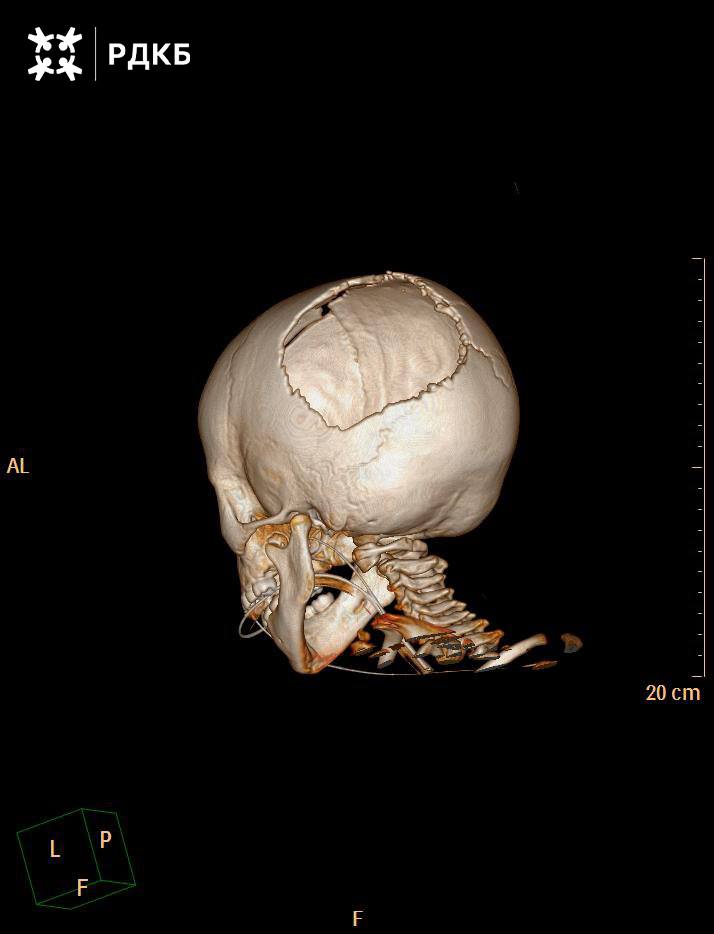

Врачи рассказали, что после лечения в местной больнице у пострадавшей оставался существенный дефект черепа в левой затылочной части. Чтобы его убрать, изготовили титановый имплант размером 12 на 14 сантиметров и установили его во время операции. По словам специалистов, конструкция импланта такова, что ребенку не потребуются новые хирургические вмешательства по мере роста.